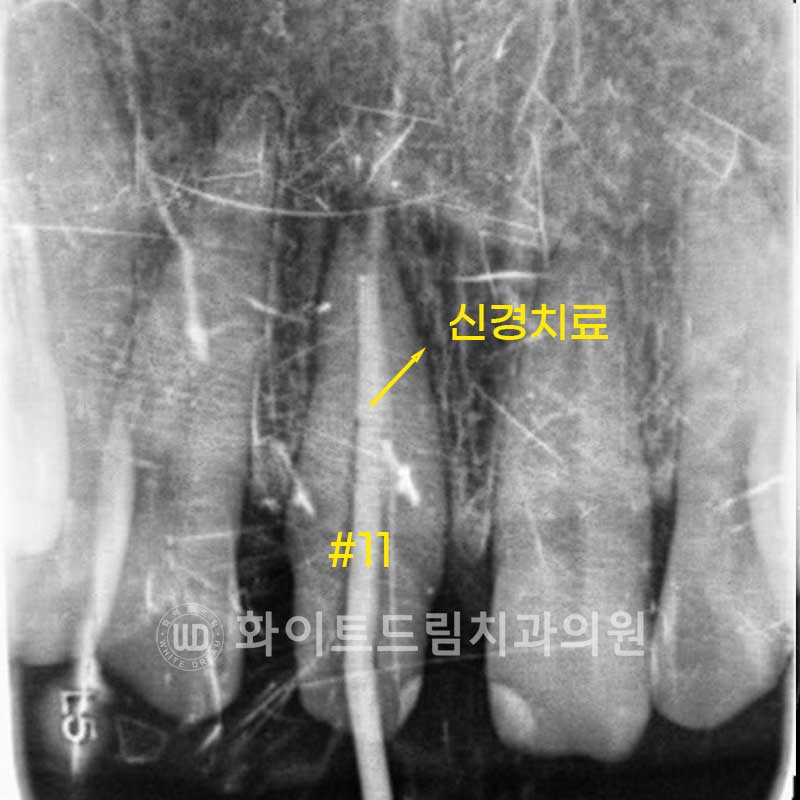

이 치아 뿌리 염증을 치료하기 위해서는 신경치료를 진행해야 합니다.

치아 뿌리 염증이 발생했다는 것은 세균이 내부 신경관을 오염시켰다는 것으로 볼 수 있습니다.

신경관 내부에 세균이 증식한 상태이기에

근관 내부에 세균을 제거하고 소독, 밀봉을 해야 하죠.

신경치료는 원래 1주일 단위로 2-3회의 반복 내원이 필요합니다.

오염된 근관을 반복 소독하여 내부를 깨끗이 청소, 밀봉해야 하기 때문이죠.

하지만 앞니는 어금니와 다르게 신경관이 1개인 단일 근관이고

근관도 휘어지거나 곡선이 아닌 직선적인 근관 형태를 띠고 있어

당일 신경치료를 진행할 수 있답니다 .^^V

▲ 앞니 당일 신경치료, 신논현라미네이트 (25.02.11)

충치로 치아 뿌리 염증이 발생한 11번 치아는 당일 신경치료를 진행한 뒤